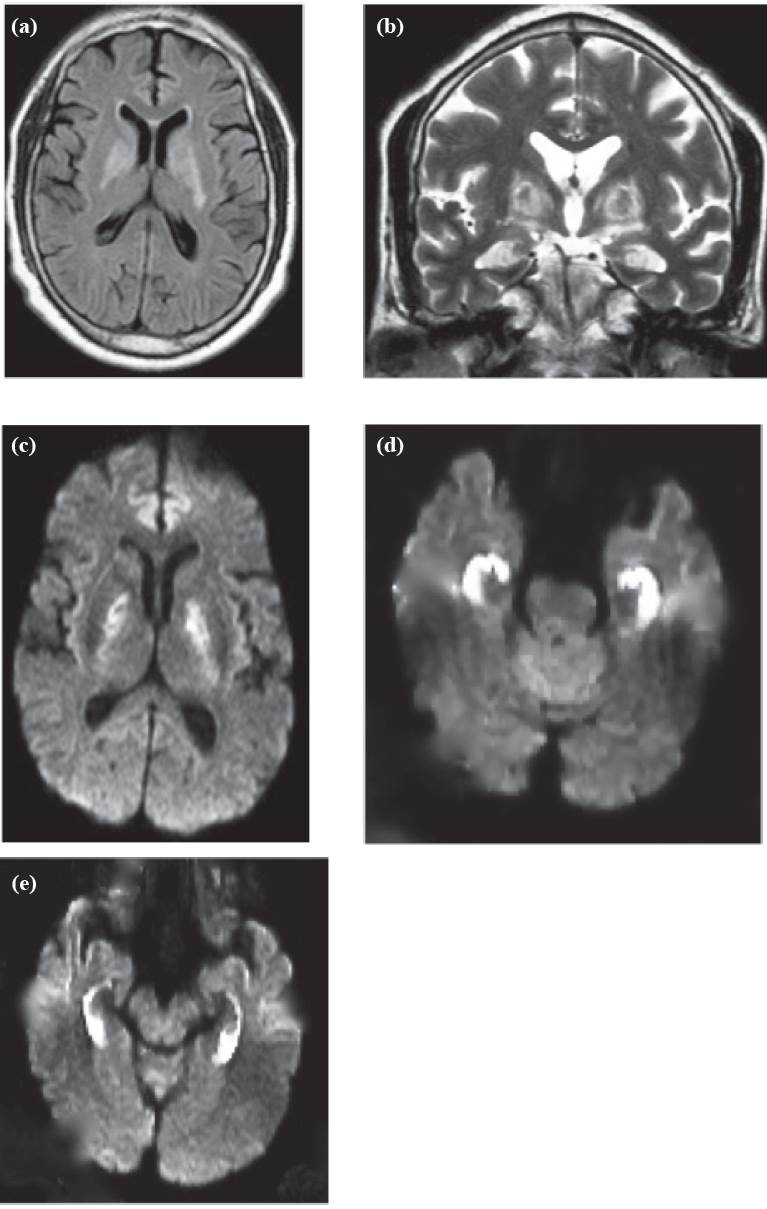

En el examen de ingreso lo encontraron inconsciente, sin respuesta verbal, ni apertura ocular, pero con respuesta motora normal; los signos vitales eran normales. No presentaba signos focales neurológicos. La TAC de cráneo simple de ingreso mostró lesiones hipodensas simétricas de los globos pálidos; incidentalmente se identificó una calcificación cortical temporal derecha (figura 1).

TAC de cráneo simple: lesiones hipodensas simétricas de los globos pálidos.

Figura 1: TAC de cráneo simple: lesiones hipodensas simétricas de los globos pálidos.

Fuente: autores.